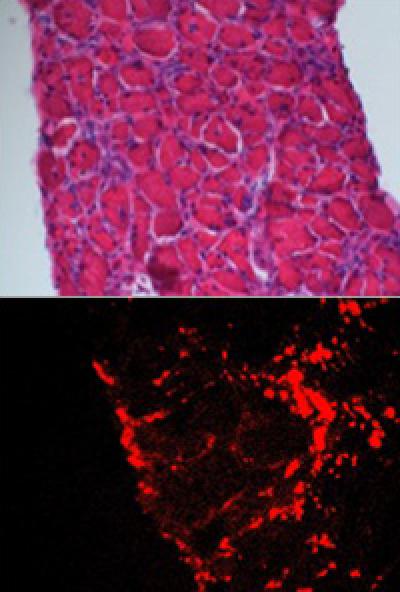

Researchers at Washington University School of Medicine in St. Louis have demonstrated a new approach to treating muscular dystrophy. Mice with a form of this muscle-weakening disease showed improved strength and heart function when treated with nanoparticles loaded with rapamycin, an immunosuppressive drug recently found to improve recycling of cellular waste.

The faulty gene that causes the disease prevents the body from producing dystrophin, a protein crucial for maintaining muscle cell integrity and function. The new study demonstrated that mice with muscular dystrophy, in addition to missing dystrophin, also can't recycle cellular waste, a process known as autophagy, or self-eating.

Though it's not clear how the missing dystrophin protein might be responsible for the muscle cells' poor housekeeping, the study showed that boosting autophagy improved skeletal muscle strength and heart function in these mice.

When treated with rapamycin nanoparticles, the mice showed a 30 percent increase in grip strength and a significant improvement in cardiac function, based on an increase in the volume of blood the heart pumped.

When injected into the bloodstream, according to Wickline, the nanoparticles accumulate in areas of inflammation, where damaged tissues have leaky blood vessels and are undergoing cell death and repair.

"The nanoparticles tend to penetrate and be retained in areas of inflammation," Wickline said. "Then they release the rapamycin over a period of time, so the drug itself can permeate the muscle tissue."